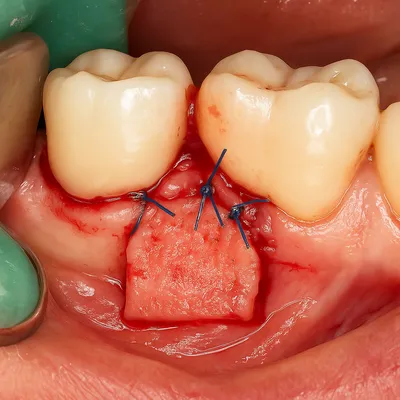

عقبرفتگی لثه و التهاب اطراف پایه ایمپلنت دندان

درمانهای جراحی

پیوند لثه (Gum Graft) برای بازسازی بافت نرم و پوشاندن ریشه نمایانشده.

در موارد پیشرفته، ترمیم استخوان فک و بافت نرم جهت جلوگیری از تحلیل بیشتر.

جراحی پیوند لثه برای ترمیم عقبرفتگی و التهاب بافت دهان